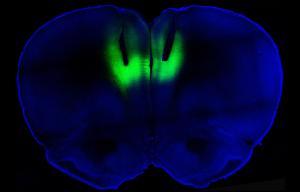

Para saber si esas neuronas inactivas a su vez generaban el comportamiento compulsivo, los científicos recurrieron a una técnica llamada optogenética, que utiliza la luz para activar neuronas dentro o fuera. Los investigadores inyectaron a las ratas virus que insertan moléculas sensibles a la luz en las neuronas perezosas. Cuando los investigadores usaron rayos láser para estimular las neuronas en las ratas compulsivas, están empujaron las palancas a un tercio de la frecuencia. El mismo experimento en usuarios no compulsivos no tuvo ningún efecto.